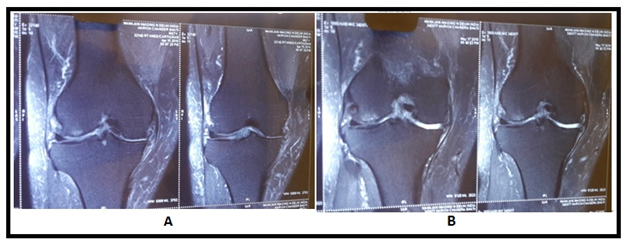

Figure 5 MRI Images showing healing pattern in cartilage breach. (A) MRI Images showing more breach in articular cartilage before stem cell transplantation, (B) images show reduced breach in articular cartilage after stem cell transplantation.

The MRI study at the last follow−up visit (1 year) showed an important improvement in the cartilaginous tissue in different parameters. Patients showed partial restoration of medial joint space of knee with disappearance of subchondral bone edema with increased thickness of articular cartilage which was more smooth and non porous in contrast to pre BM−MSC transplant stage. The pre and post BM−MNCs transplant MRI/x−Ray studies showed notable changes in cartilage defects (Figures 4‒8).